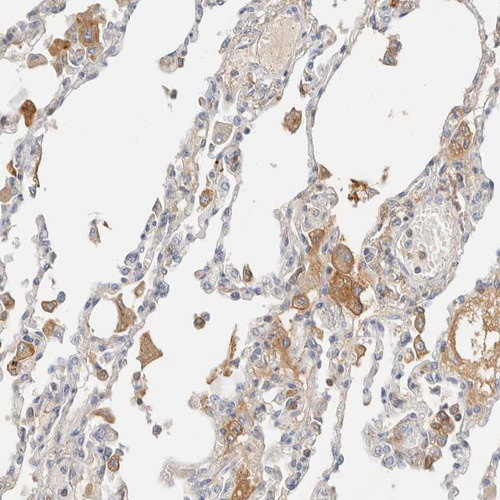

Immunohistochemistry analysis in human liver and cerebral cortex tissues using HPA023694 antibody. Corresponding C8B RNA-seq data are presented for the same tissues.